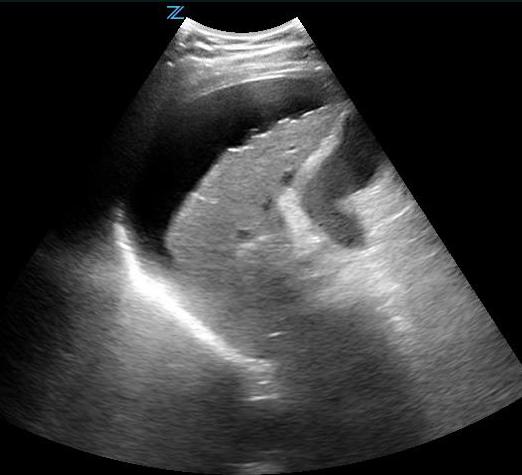

- This gives a coronal view of the interface between the liver and kidney. (Fig. 5) It is important to follow the lower edge of the liver caudally until a good view of the liver tip is obtained as fluid will often collect there first. (Video 4)

- Free fluid is usually seen in Morison’s pouch or along the lower edge of the liver and around the lower tip of the liver. (Figure 5, Videos 5-8)

- Figure 5. Small amount of free fluid Morison’s pouch view